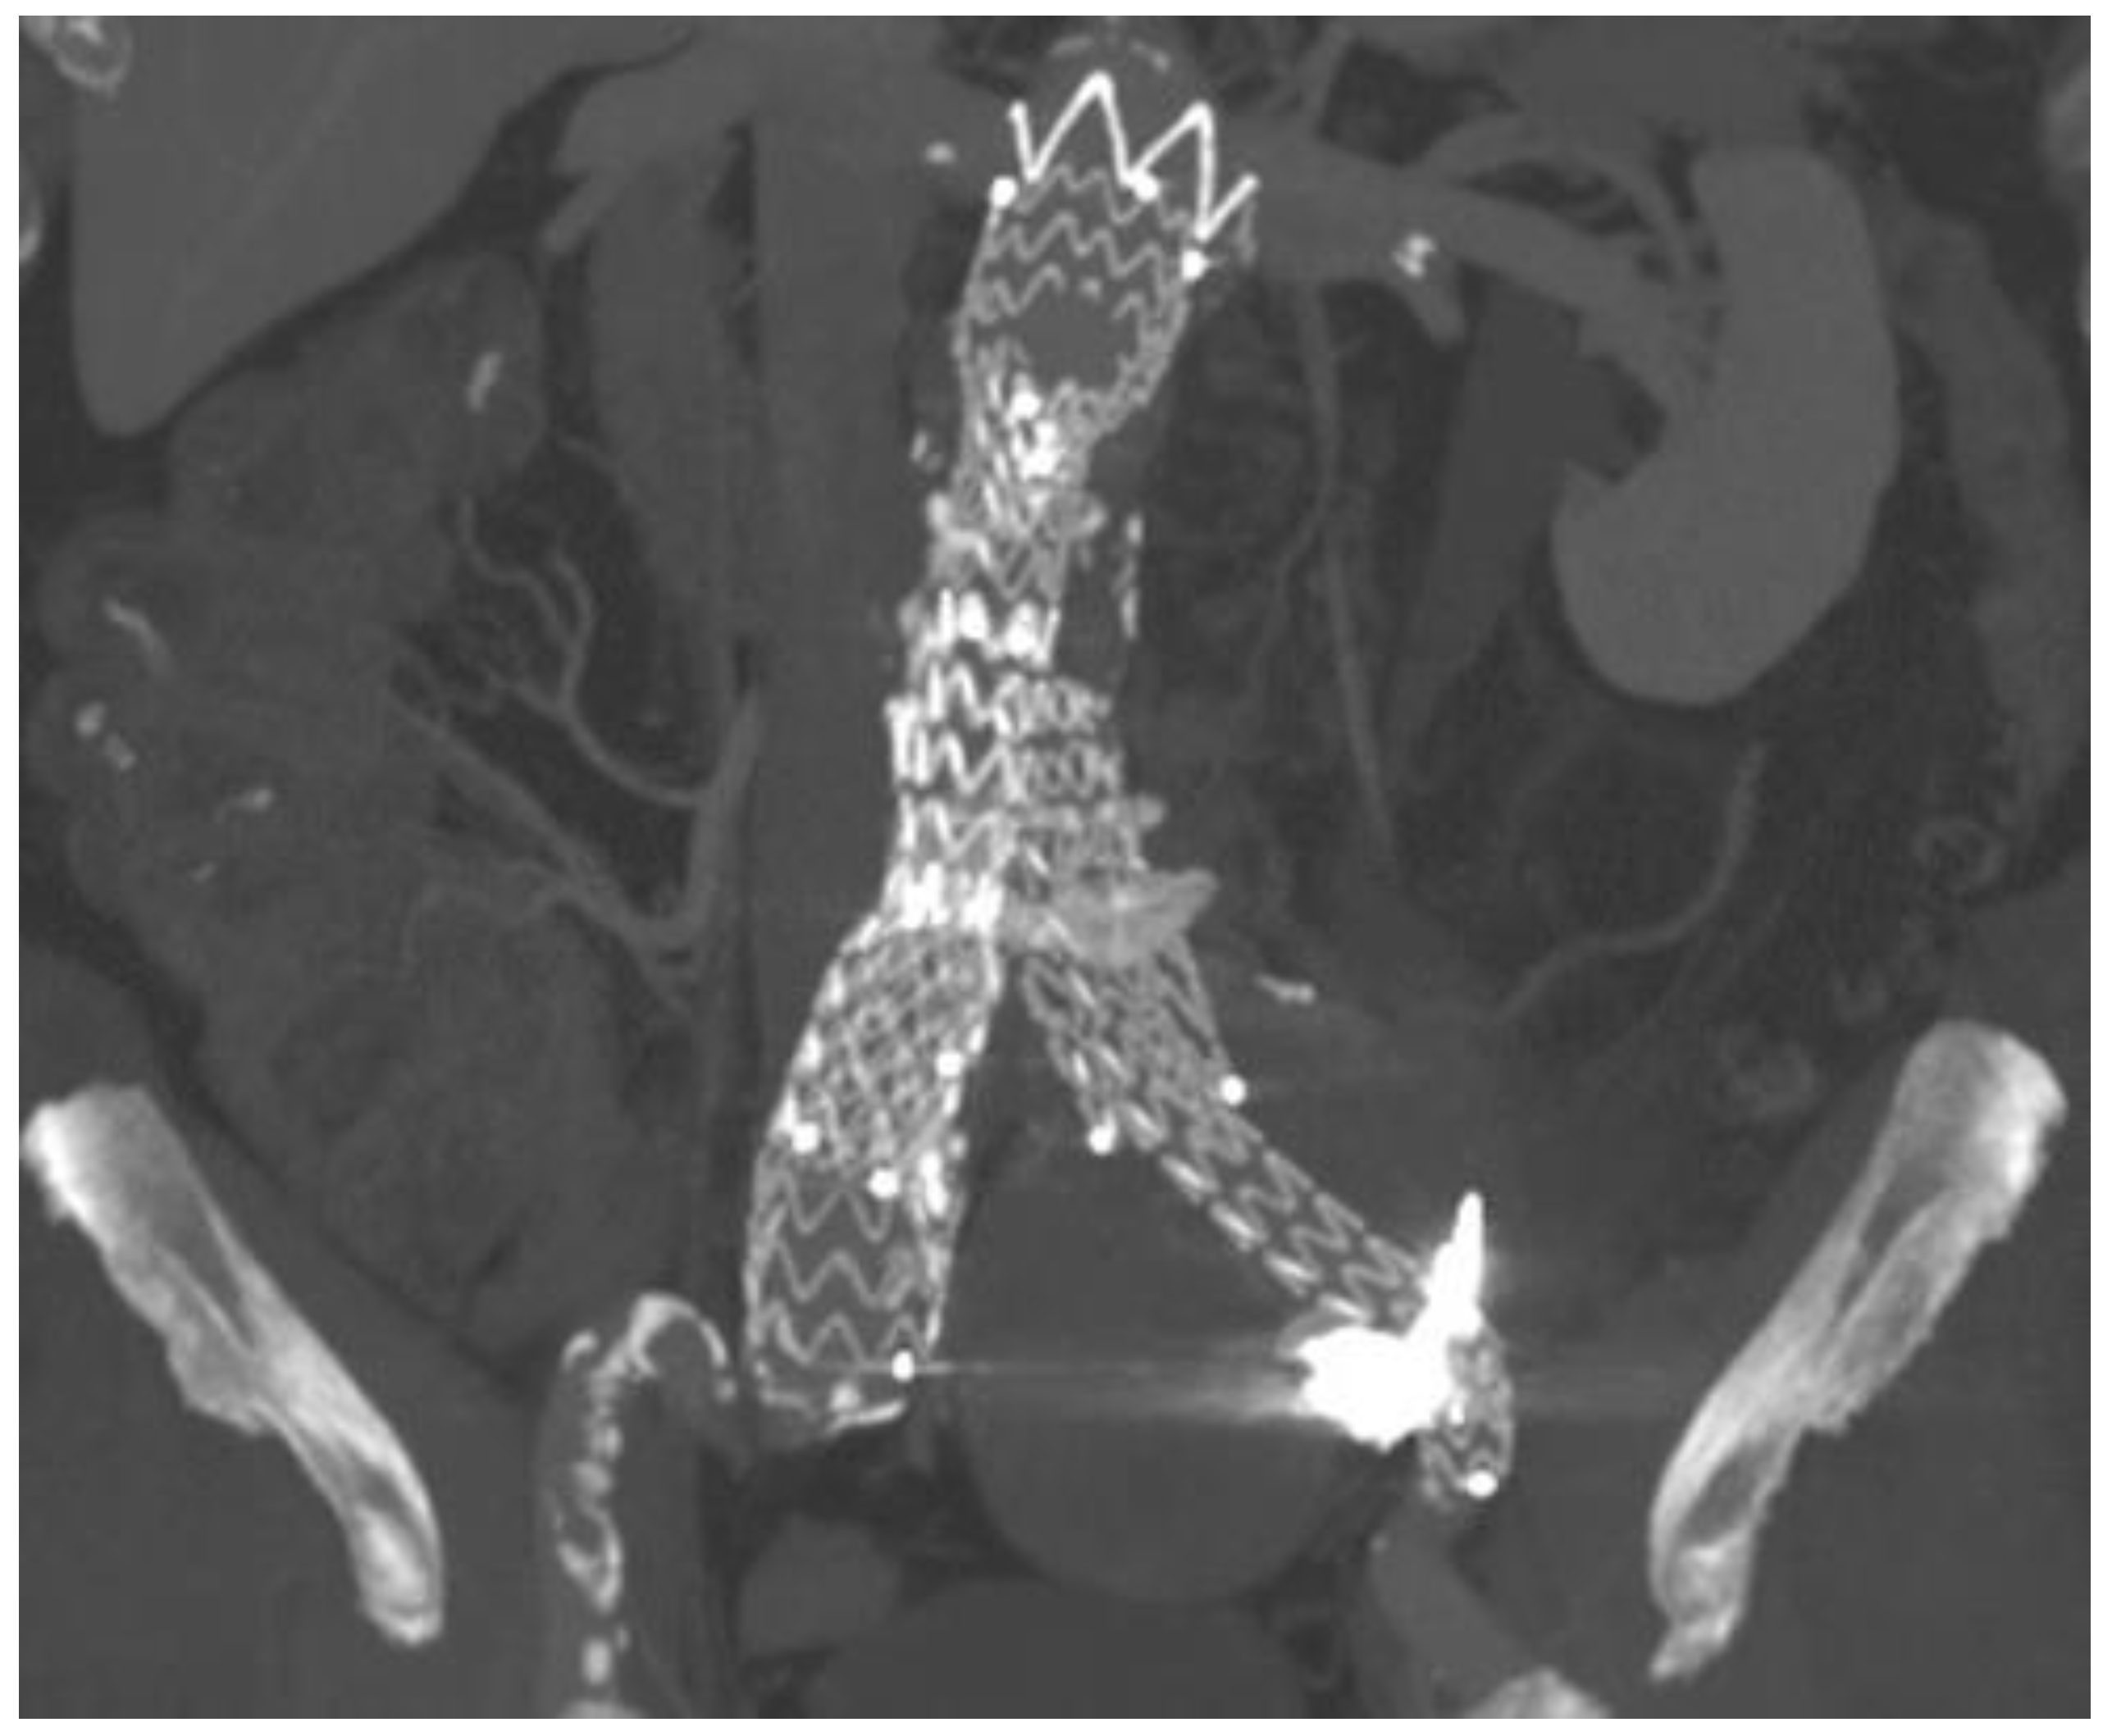

2. Case Presentation